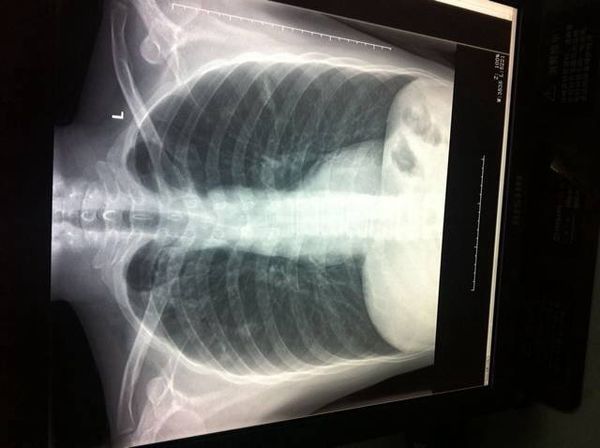

女子拍胸片,医生看到胸口有两片阴影,误以为是

816x825 - 73KB - JPEG

肺部阴影通常是指在透视中发现肺实质内有高密度区,在胸片上或CT上常表现为肿块或结节,一般肿块的标准是

体检结果里写着“肺部有阴影”,这意味着你的肺部可能有病变了,当然也像肺炎、肺脓肿、肺结核等拍胸片都

胸片肺部有阴影通常都是发生在现肺实质内有高密度区,通常情况下很有可能是属于肺部肿块还是结节。